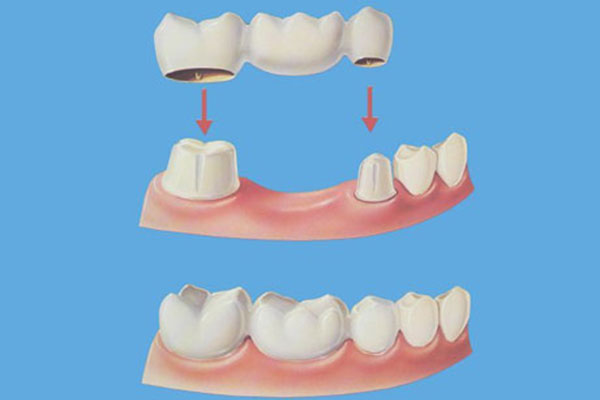

بریج دندان یکی از روش های قدیمی رفع مشکل نداشتن دندان است که از طریق آن می توان چای خالی یک یا چند دندان را پر کرد. پل دندان باعث ایجاد زیبایی بیشتر دندان ها می شود، چرا که با پر کردن فواصل بین دو دندان نقش بسزایی در افزایش زیبای طرح لبخند دارد. این روش که از اسمش پیداست (بریج دندان)، مثل یکی پل عمل کرده و از طریق قرار دادن روکش مصنوعی و دندان مصنوعی، دو دندان را به یکدیگر وصل میکند. دندان مصنوعی با کمک دو دندان اطراف روکش شده سر جای خود محکم باقی می ماند.

وقتی که یکی از دندان های از بین می رود ولی دندان های اطراف آن سالم است، دندان پزشک از روش بریج دندان استفاده کرده و باعث میشود تا شکل دندان های که از نظر ظاهری ناخوشایند است را به فرم روز اولیه خود برگرداند. جنس دندان مصنوعی به کار رفته می تواند از جنس سرامیک، طلا و یا آلیاژهای دیگر باشد.

- در مرحله اول در صورتی که دندان های اطراف فضای خالی، سالم باشد دندان پزشک آن دو دندان را برای قرار دادن روکش آماده می کند اما اگر این دو دندان به منظور حمایت از دندان مصنوعی مناسب نباشد، دندان پزشک مجبور می شود از طریق جراحی، ایمپلنت هایی را درون لثه قرار دهد.

- در مرحله دوم دندان پزشک از دستگاهی برای تشکیل روکش دندان های اطراف فضای خالی و دندان مصنوعی استفاده میکند. به روکش دندان و دندان مصنوعی، بریج گفته می شود.

- در مرحله اخر، بریج موقتی برداشته شده، و بریج های تشکیل شده بر روی دندان ها، چسبانده می شود.